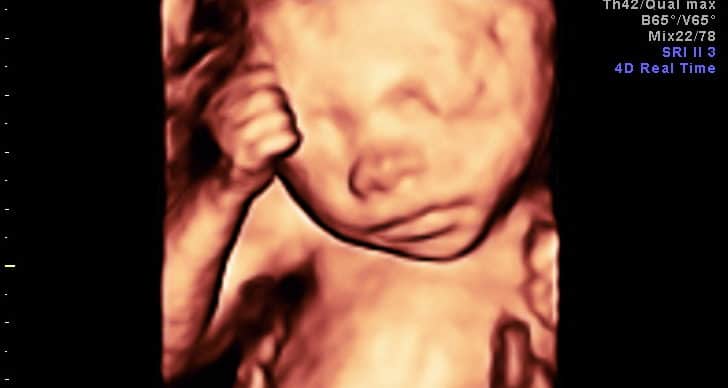

O Bebê Seu corpo começa a produzir glóbulos brancos para combater as infecções. Os pulmões estão mais desenvolvidos, porém ainda…